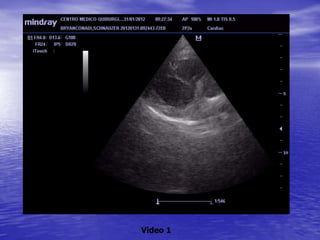

ECOCARDIOGRAFIA

Video 1